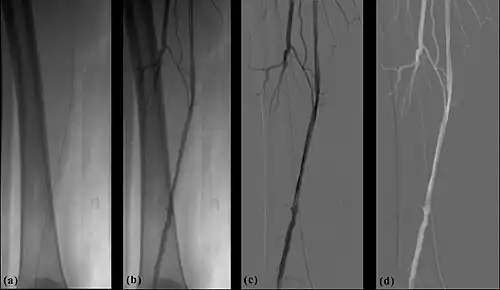

- The temporal-averaging feature of digital noise reduction can also be used for image presentation purposes so that the time course of the movement of contrast medium during a study can be displayed using just one image - see an example in Figure 7.4 from the peripheral study shown above - instead of a sequence of numerous images. Such an image is sometimes referred to as a Vascular Trace.

- One method of temporal filtration, referred to as Integrated Mask-Mode DSA involves adding (also called integrating) a number of images, acquired prior to the arrival of the contrast medium, to form an integrated mask image and adding a number of peak-opacification images to form an integrated live image. This is the process that was used to generate the vascular trace image in Figure 7.4. Thus, when four images are used to generate each integrated mask and live images, eight of the 25 images are now used in the subtraction process and, as a result, only 68% of the dose is wasted, and a subtraction image with lower noise results.

- Additional processes involve Bolus Chasing, Rotational Angiography and Volume Tomographic Angiography. Bolus Chasing[28] has been found to be particularly helpful in peripheral angiography, for example. Here, the progress of the contrast medium is tracked automatically and used to increment the table and/or XRT/image receptor movement to the next anatomical region. The subsequent set of subtraction images can then be used to construct a composite image of the peripheral vasculature. In Rotational Angiography[29], a C-arm assembly, for example, can be caused to rotate at 10 - 30 degrees per second during the imaging sequence. Subsequent dynamic display of the subtraction images can be used to generate a perceived 3D presentation so that complex relationships within the vasculature can be more readily appreciated. Volume Tomographic Angiography[30] is similar to Computed Tomography (CT) where the C-arm is rotated around the patient during the imaging sequence. The image data is subject to a volume reconstruction algorithm which permits generation of three-dimensional images of the opacified vasculature. We will consider this latter process in more detail below.